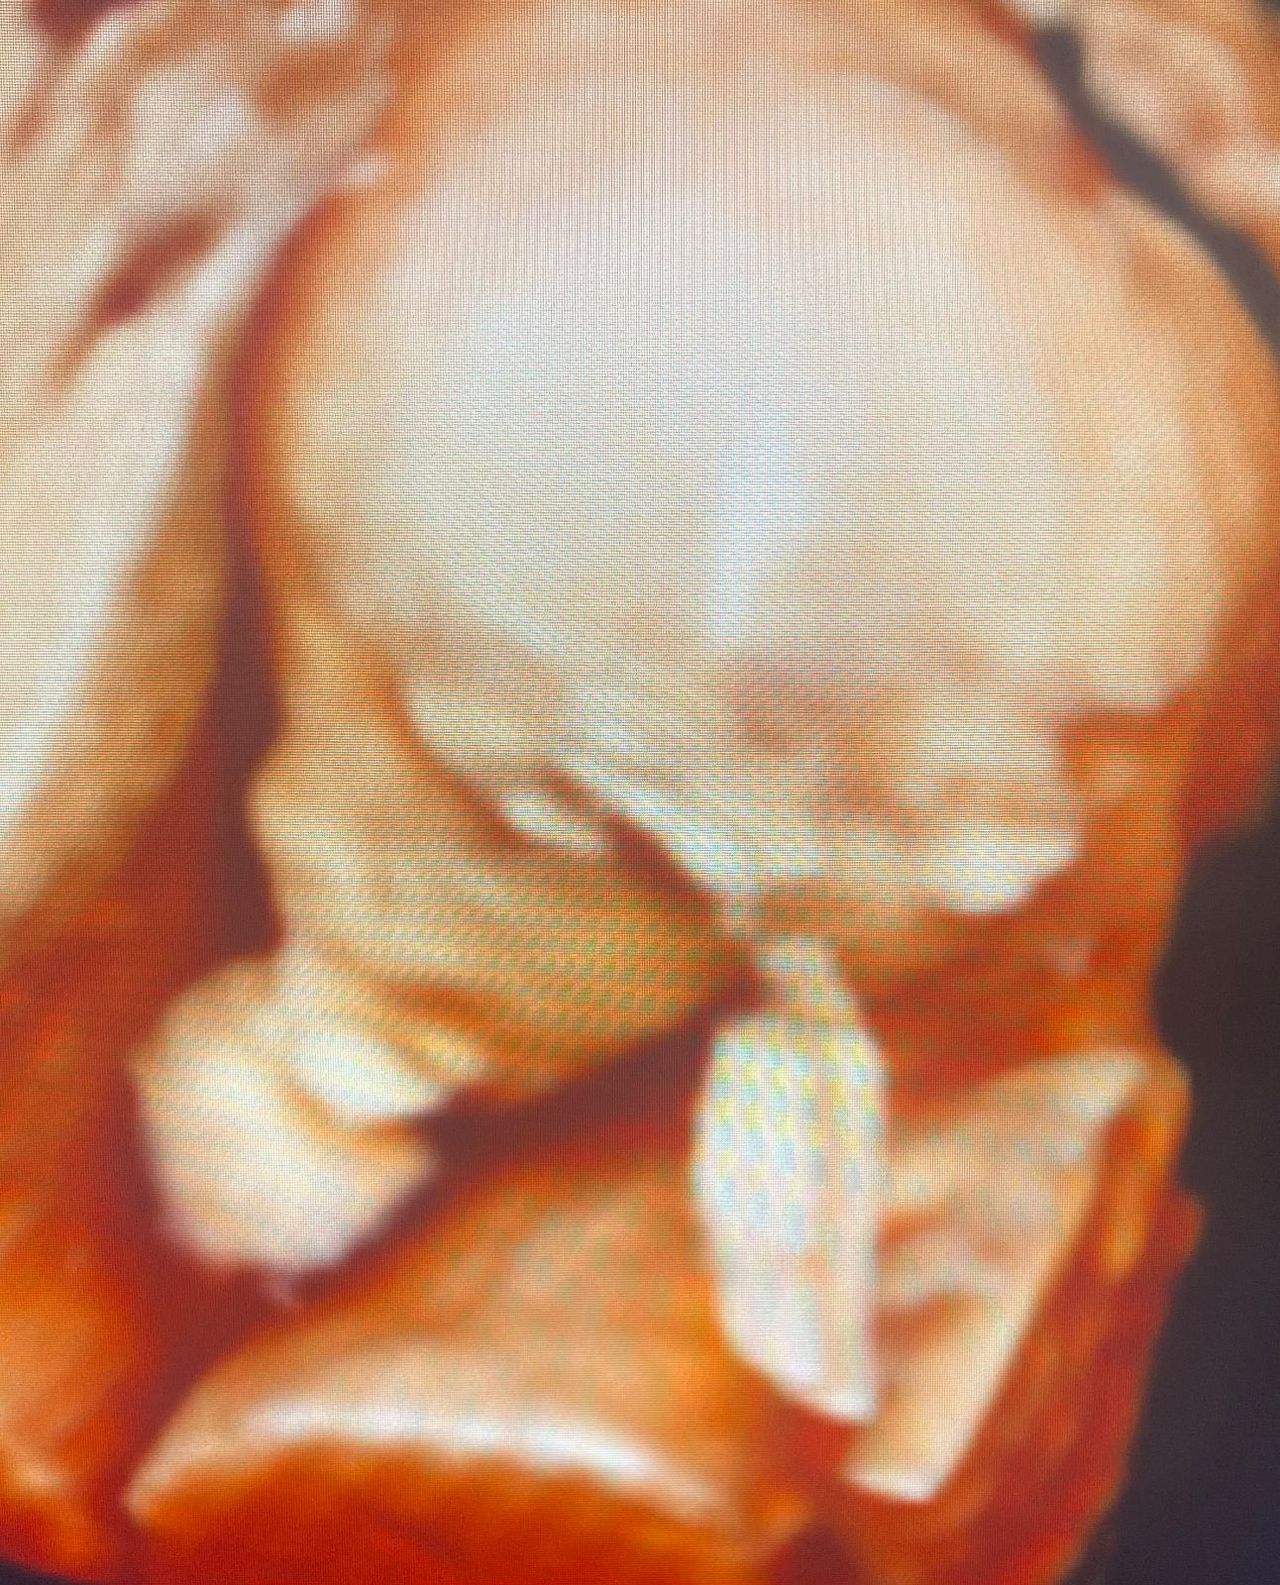

Ultrasonido obstétrico

$600